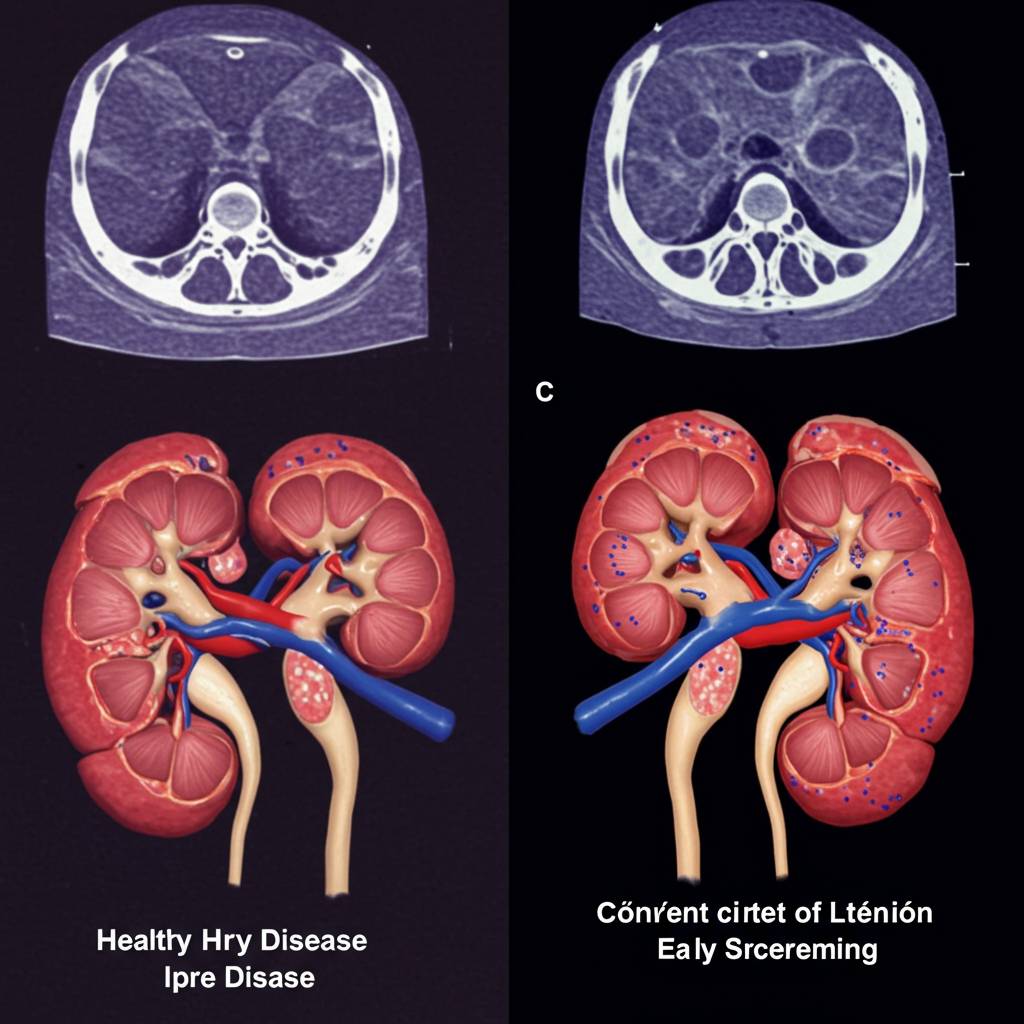

腎臓の異変は静かに進行することが多く、「サイレントキラー」と呼ばれることもあります。多くの患者さんが症状を自覚した時には、すでに病気がかなり進行していることも珍しくありません。実際の症例から、早期発見がいかに重要かを見ていきましょう。

腎臓病の進行は静かで、初期症状がほとんど現れないことが特徴です。多くの患者さんが症状を自覚した時には、すでに病状がかなり進行していることが少なくありません。実際の症例を見ると、定期的な健康診断で偶然発見されたケースが早期治療につながり、腎機能の低下を最小限に抑えられています。